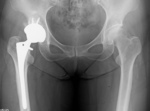

年代が若い時の股関節の悩みは、写真の左側になる。

右側は変形が進み『手術』という言葉が選択肢として出てくる。